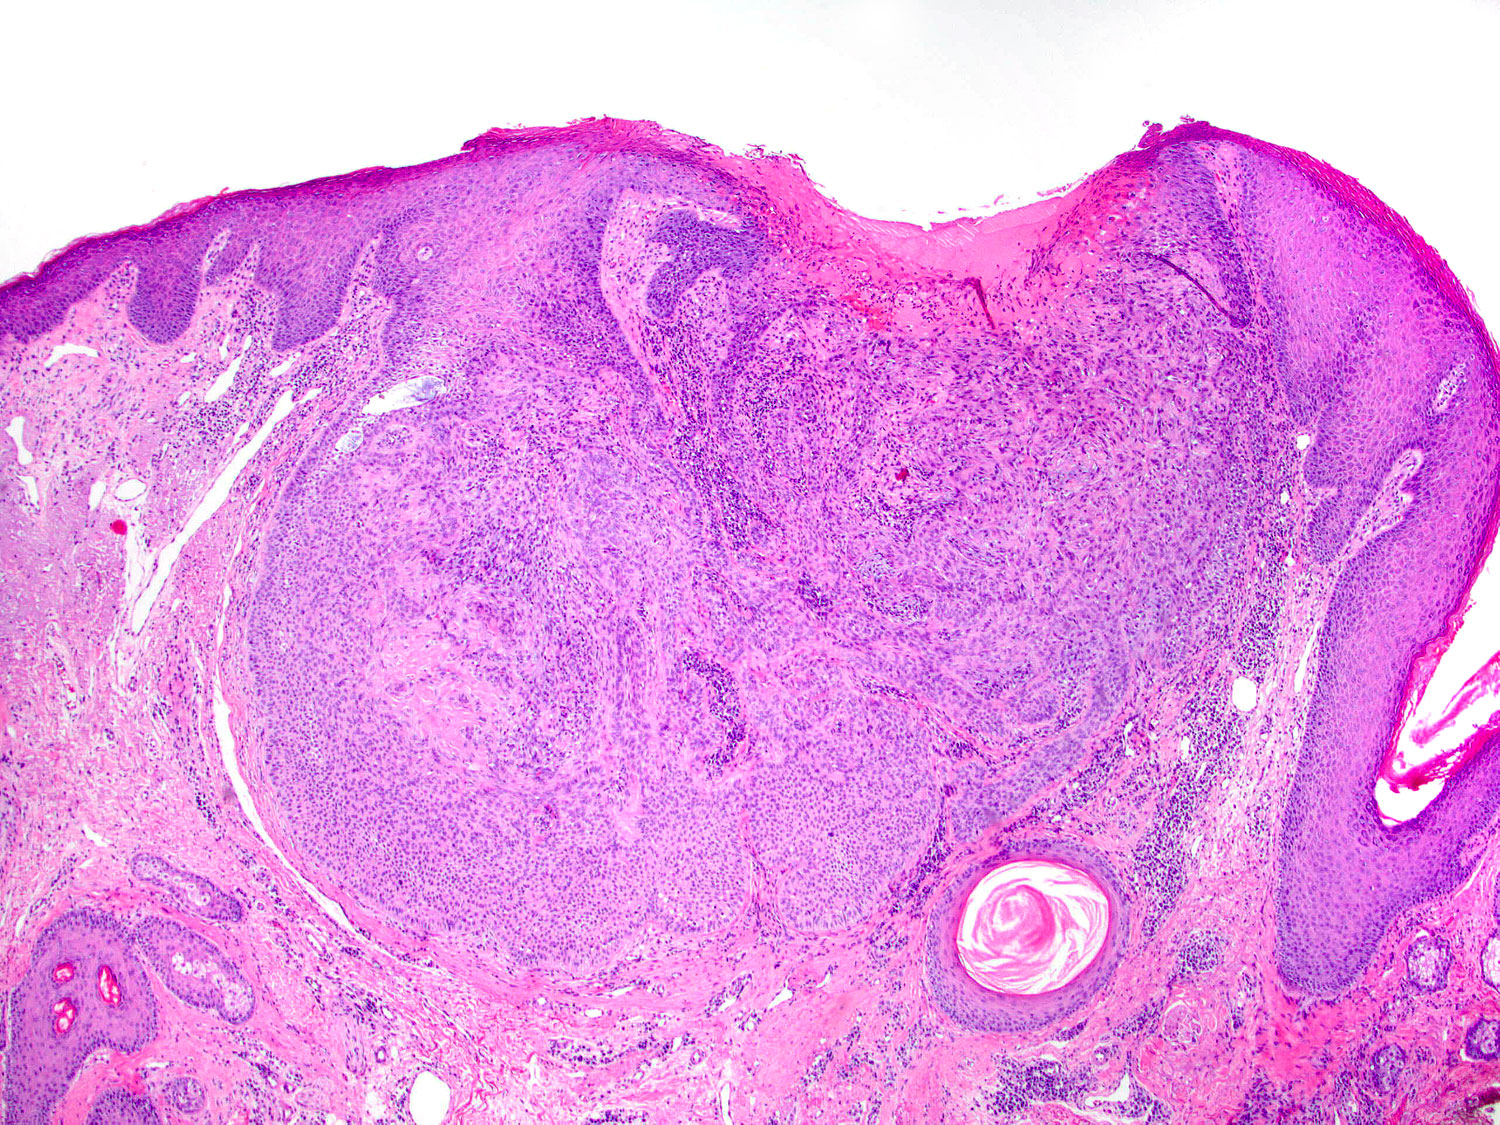

H&E staining (4x objective)